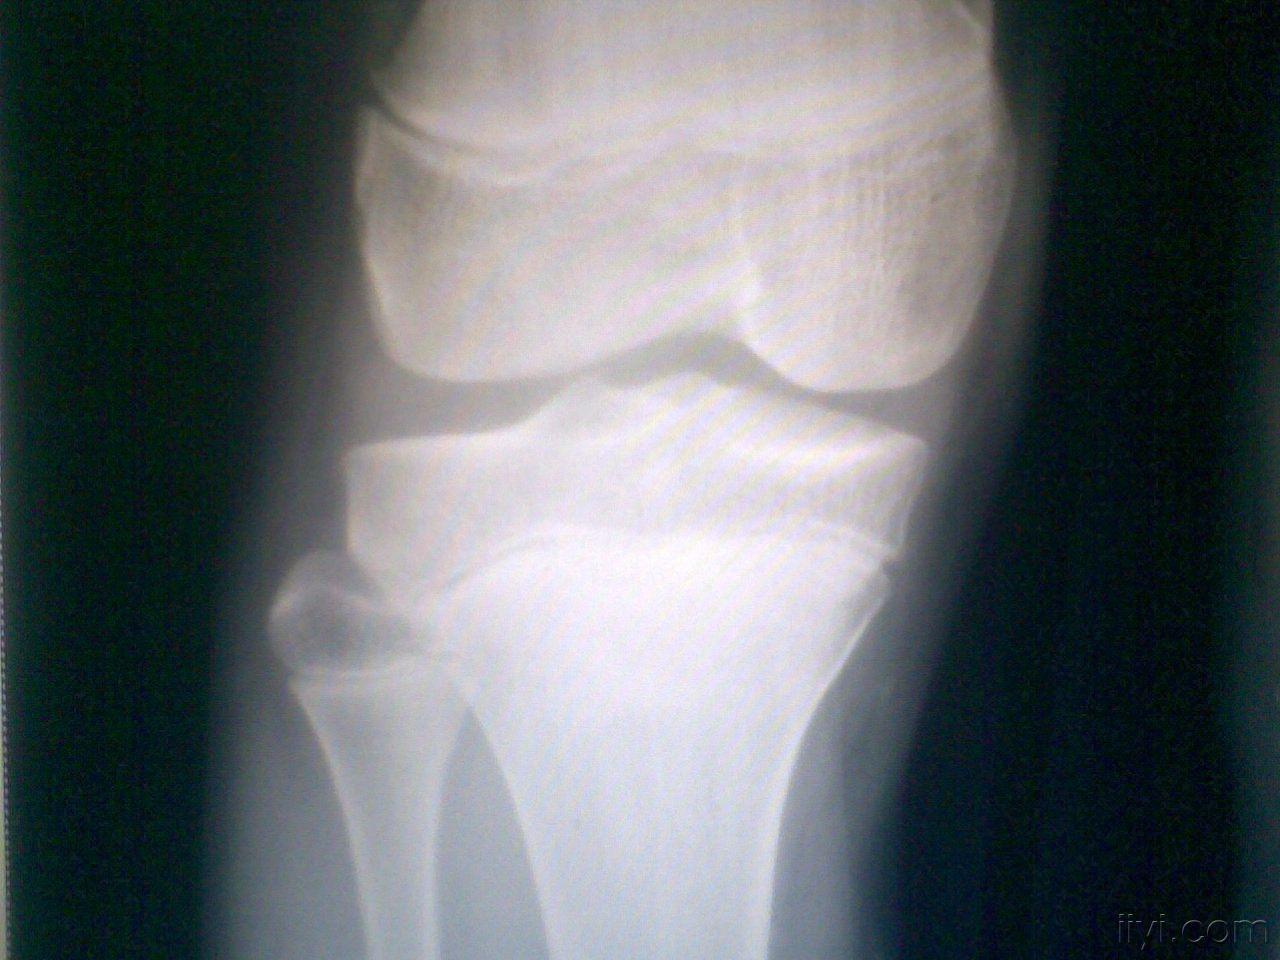

正常的膝关节影像图片

正常的膝关节影像图片,正常膝关节x线图片

膝关节正常解剖及常见病变的影像表现

正常膝关节x线图片

正常膝关节x光片图

正常的膝关节x片图片

正常膝关节x光片

正常膝关节x片